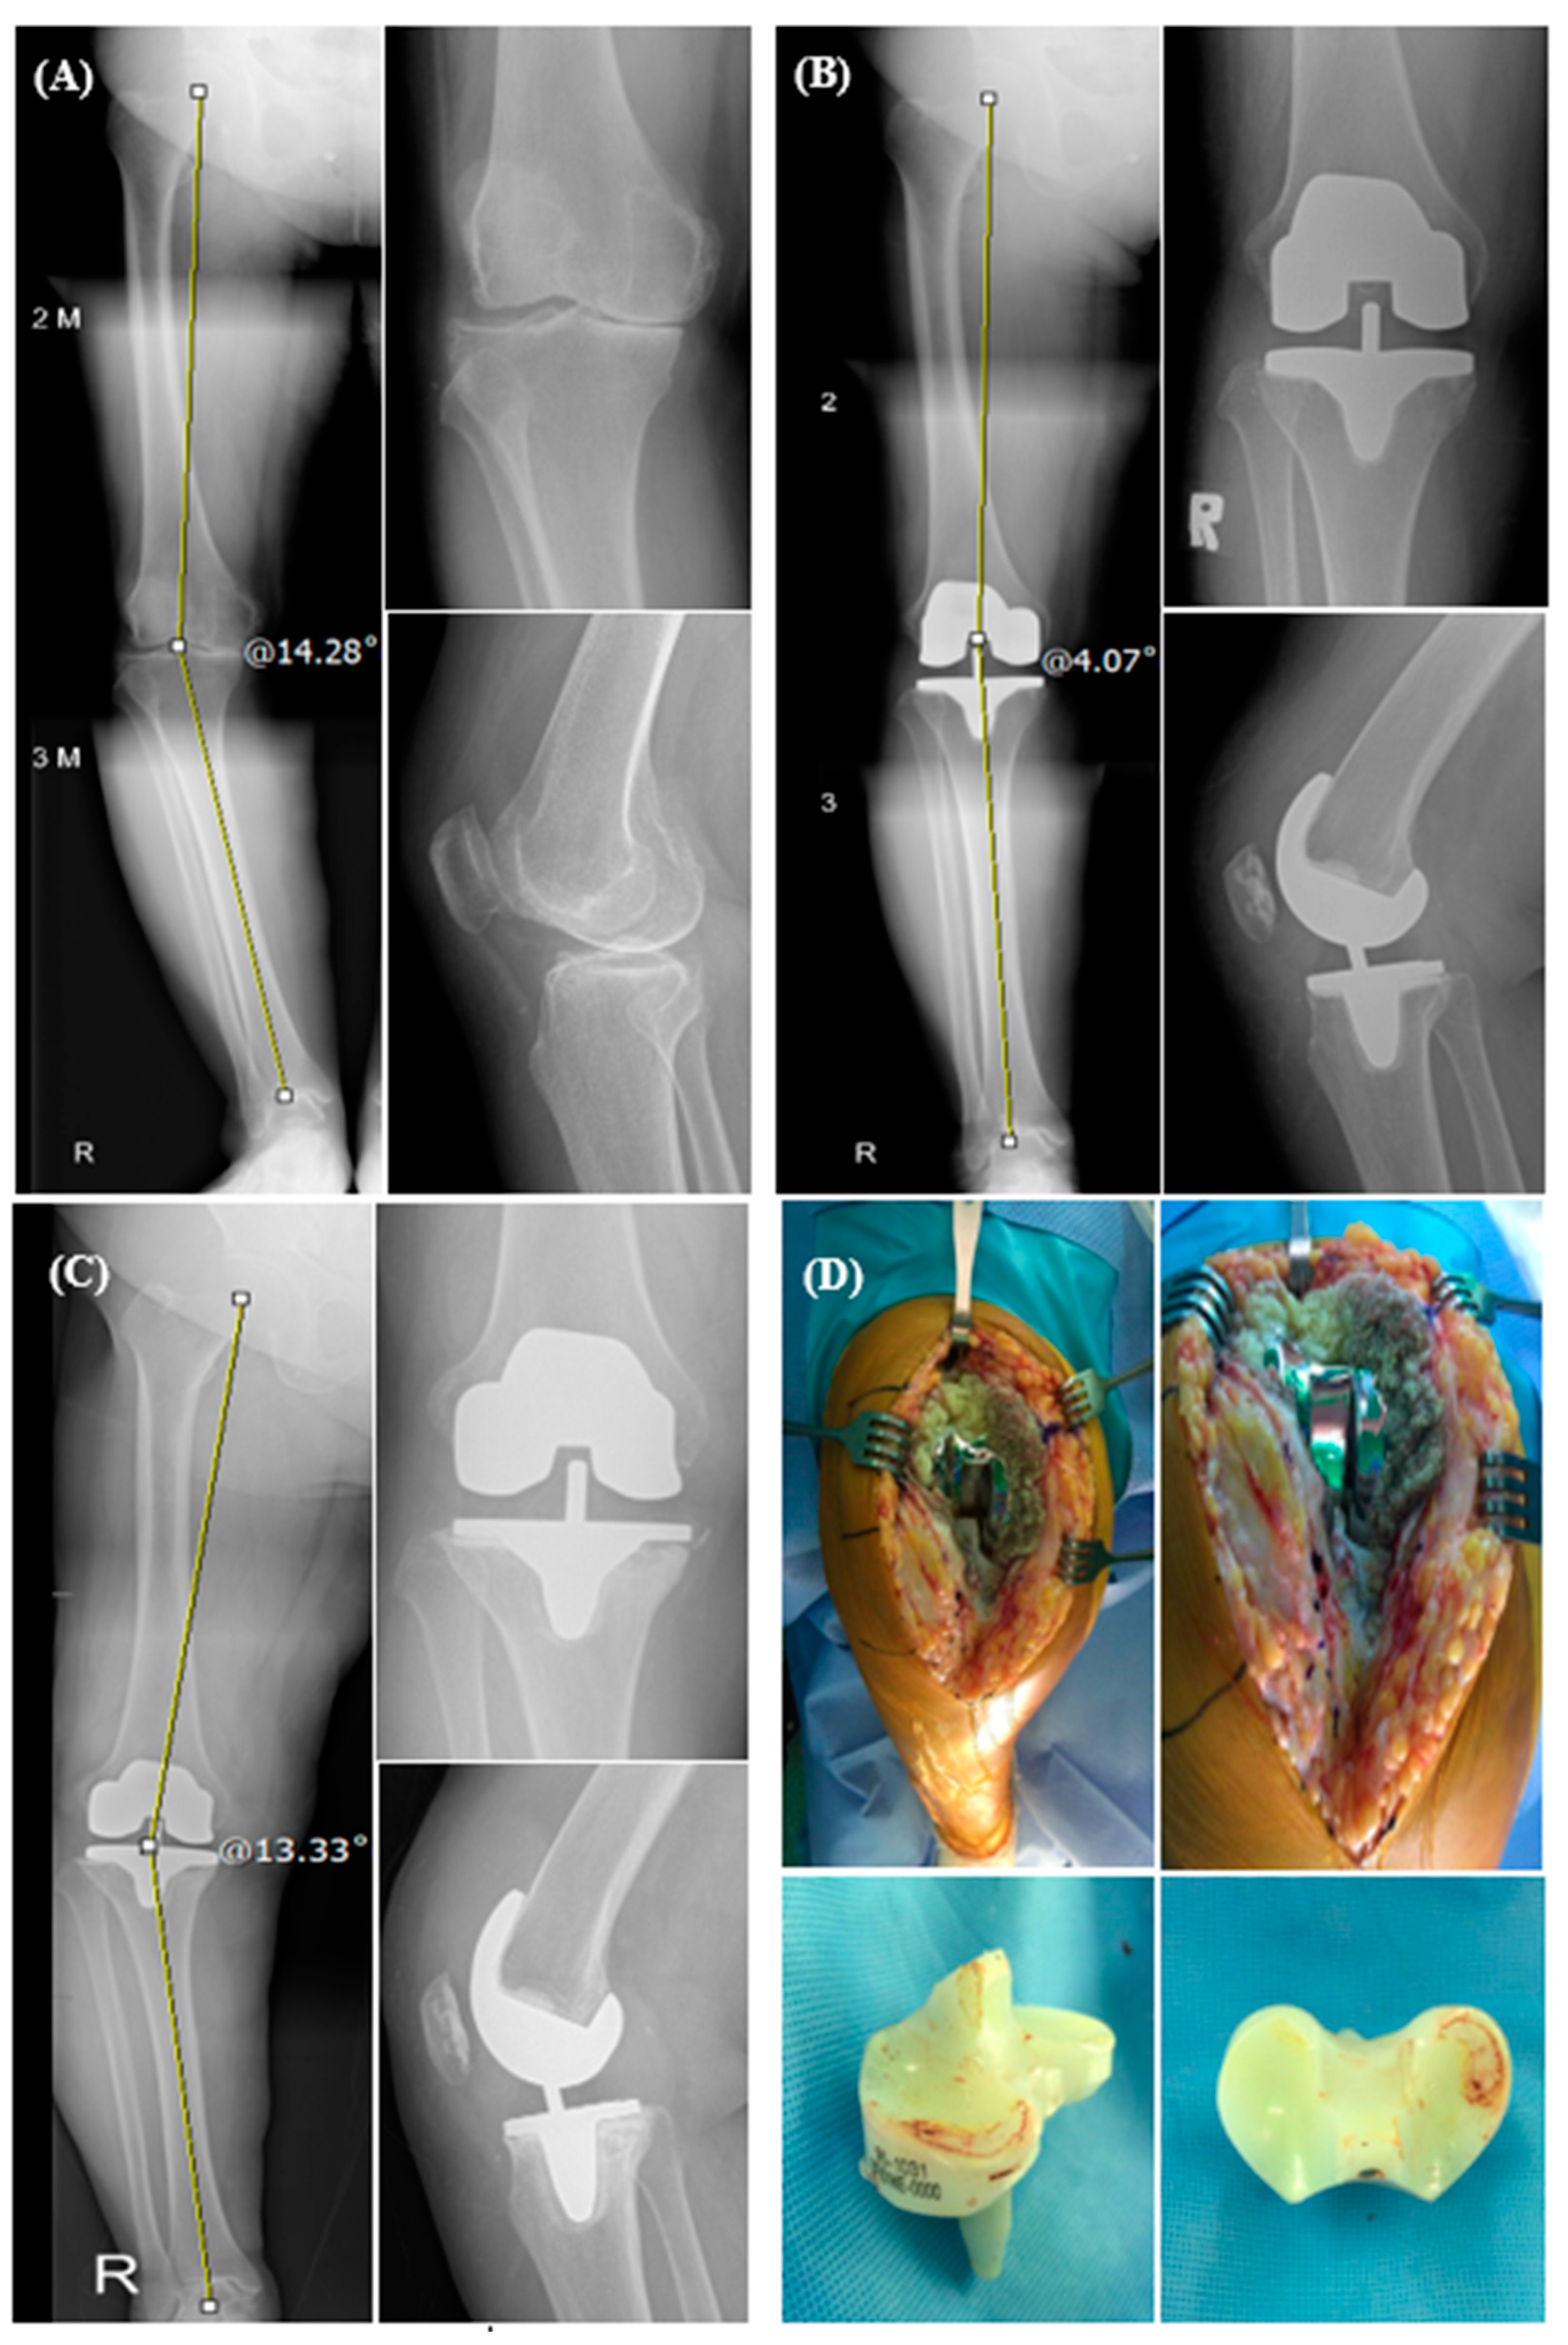

| HKA angle (°) | |||

| Preoperative | 11.49 ± 6.09 | 12.00 ± 4.17 | 0.651 |

| At latest follow-up | 2.40 ± 3.86 | 1.61 ± 2.59 | 0.267 |

| Component position | |||

| α angle (°) | 95.62 ± 2.59 | 95.87 ± 1.76 | 0.600 |

| β angle (°) | 90.81 ± 3.59 | 90.40 ± 2.43 | 0.532 |

| γ angle (°) | 4.26 ± 0.57 | 4.08 ± 0.76 | 0.193 |

| δ angle (°) | 84.24 ± 2.77 | 83.50 ± 2.11 | 0.161 |